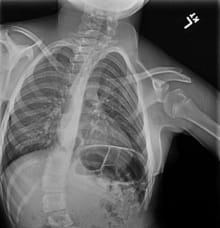

Paige’s spine before surgery

Paige Williams, 11, the second patient successfully treated at UH with FIREFLY®, had worn a brace or cast for most of her life due to congenital scoliosis (curvature of the spine) and other vertebrae abnormalities. In addition to limiting her ability to move and play, Paige’s crooked spine was also affecting her heart and lung function and contributing to possible hip dysplasia.

Christina Hardesty, MD, a pediatric orthopedic surgeon at UH Rainbow Babies & Children’s Hospital worked with FIREFLY® engineers to turn CT scans of the young patient's spine into an anatomically matched 3D-printed model, giving Dr. Hardesty a clear picture of the patient's spine to help her prepare for surgery.